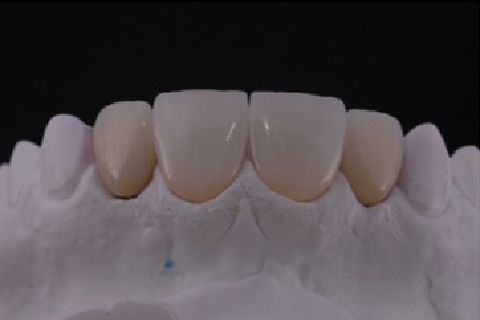

''Neste caso, a paciente gostaria de melhorar a estética do seu sorriso, prejudicada pela agenesia de ambos os incisivos laterais superiores. Devido à baixa disponibilidade óssea, observada na tomografia computadorizada, optou-se pela instalação de implantes estreitos (Xive – Dentsply Implants – 3.0 mm de diâmetro) com regeneração simultânea (Biooss e Biogide – Geistlich), ao invés de realizar enxerto ósseo prévio. Após osseointegração, foi realizado condicionamento gengival com provisórios e novo enceramento diagnóstico. O caso foi finalizado com coroas livres de metal sobre os implantes e microlaminados cerâmicos sobre os incisivos centrais (e.max - dissilicato de lítio – Ivoclar Vivadent), visando o mínimo desgaste de estrutura dental sadia. ''